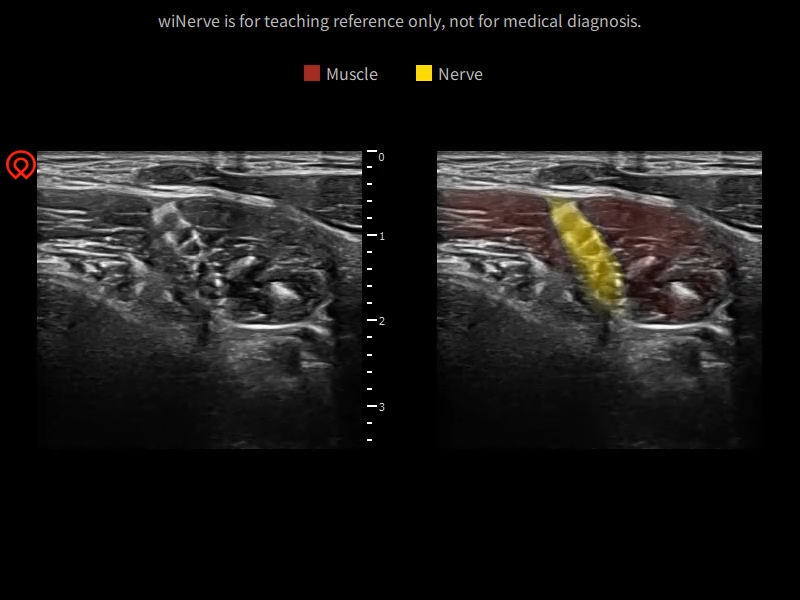

wiNerve - Reconocimiento inteligente de nervios mediante IA

Reconocimiento en tiempo real

Solución en cloud

Apoya múltiples nervios